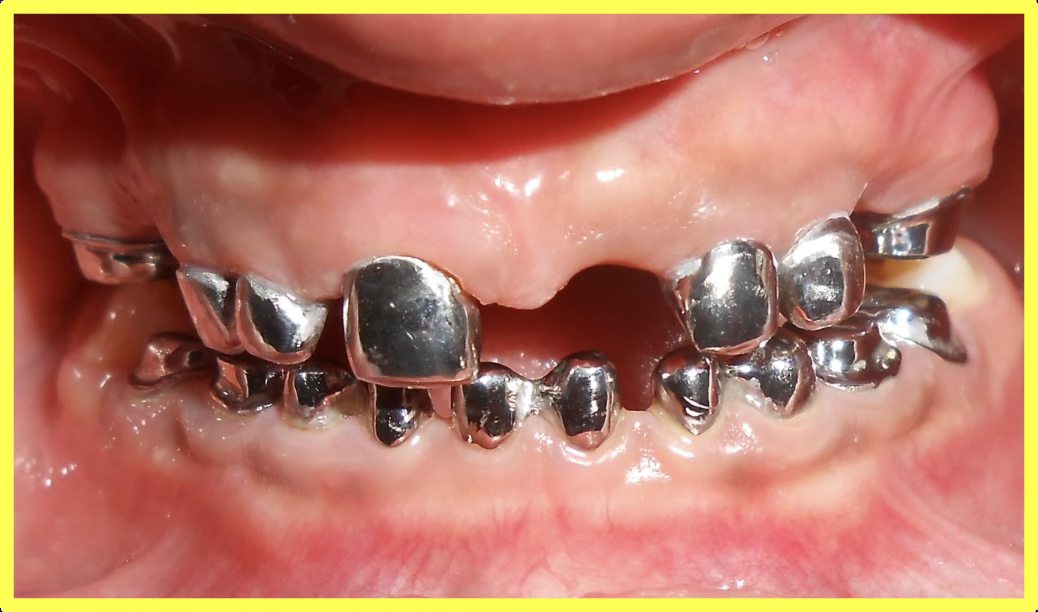

Custom telescopic copings were designed and fabricated to fit over prepared teeth, providing retention and support for the removable prosthesis.

Upper and lower telescopic removable metallic PFM prosthesis was carefully fitted, adjusted, and delivered to restore complete dental function and aesthetics.